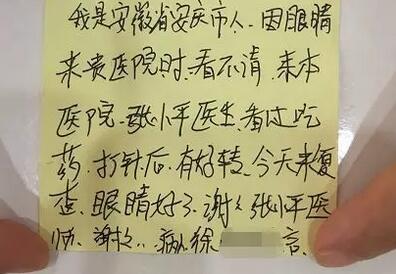

经过三次复诊后,徐先生的眼睛没有出现明显的并发症和后遗症,眼痛、畏光等眼部刺激症状明显好转,前房炎症得到了控制,前房积脓基本吸收,而且虹膜后粘连也已经被拉开,瞳孔 圆形。满怀感激之情的他复查临走时还特意写了一段感谢信要给张小平主任。